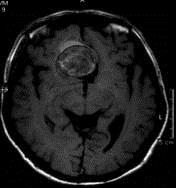

问题 病历摘要:??患者男性,56岁,因右侧视力下降伴视野缺损2个月来院就诊,诉头痛,无明显头晕,无视物重影,无恶心呕吐,无肢体抽搐,无肢体乏力,胃纳佳,大小便正常,既往史无特殊,入院检查:神志清楚,言语清楚,体毛分布正常,左侧视力4.6,右侧视力4.0,粗侧右颞侧视野缺损,左侧正常,颈软,四肢肌张力正常,肌力正常,病理征(-)。 有关巨型动脉瘤,下列说法正确的有?

选项 A.巨型动脉瘤多发生于大脑前动脉 B.发病形式有隐匿性的和突发的蛛网膜下腔出血 C.巨型动脉瘤不会出现缺血的症状 D.64%的病患者因为压迫的病灶性神经功能障碍就诊 E.该例患者夹闭瘤颈后,不须处理瘤体 F.该例患者瘤内有大量血栓形成,因此不会出血

答案 BD